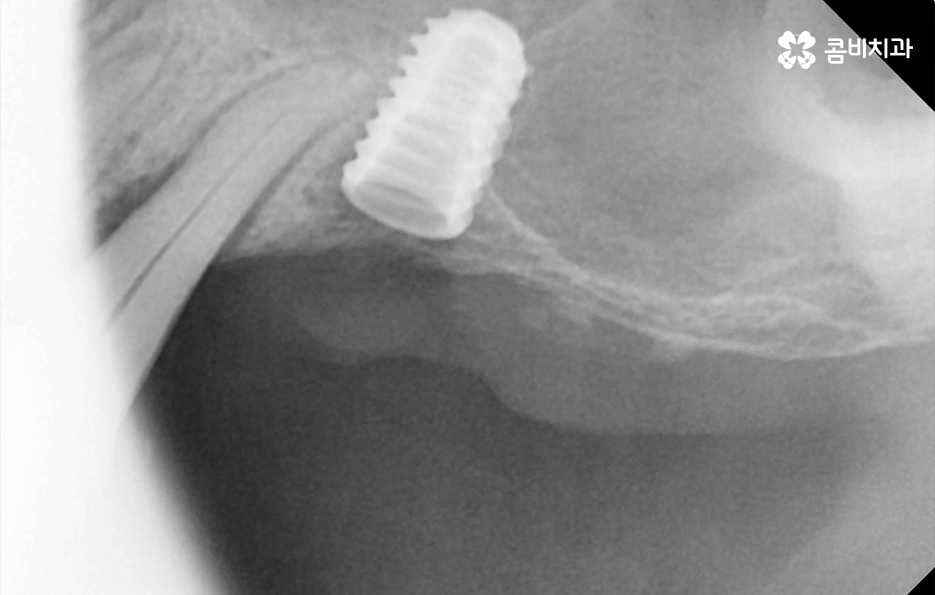

임플란트의 시술 원리는 잇몸 뼈에 식립하게 되기 때문에 충분한 골조직이 없을 때는 시술 성공률도 낮아질 뿐 아니라 장기적인 안정성도 떨어지기 때문에 잇몸 뼈가 부족하신 분들은 뼈이식을 추가적으로 해야할 수 있어요

만약 치주염으로 인해 50대임플란트 해야 하는 분들의 경우에는 뼈이식을 추가적으로 받아야 하는 경우가 있겠고 임플란트의 안정성을 확보하기 위해서는 임플란트를 고정해줄 수 있는 일정한 두께와 식립 깊이, 골질이 건강해야 하는데요

또한 뼈이식을 해야 하더라도 잇몸을 되도록 보존하는 치료를 하고 치료 시점을 의사와 잘 상의한다면 뼈이식의 양을 줄일 수 있고 회복기간도 상대적으로 줄일 수 있다는 점에서 임플란트 치료 원리를 먼저 이해하시고 대처하시길 바라고 있어요